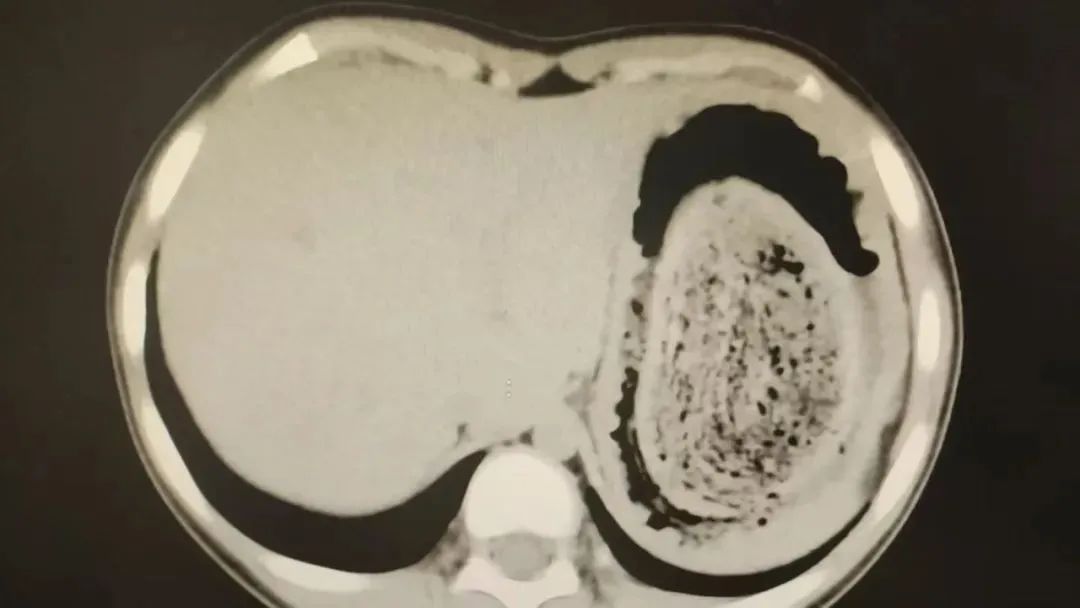

结果出来时,医生都惊呆了:小可的胃里,塞满了成团的头发,几乎占了胃容量的四分之三。大量不能消化的物质,在胃酸的作用下发生变性,并与食物及其他物质结合形成团块,慢慢变成坚硬的“胃石”。

为了避免用手术方式去除头发团聚合财富,陈攸涛先让小可喝可乐软化“胃石”,再通过胃镜辅助取出头发,整个过程花了十几个小时,清理出的头发装了两大盆。